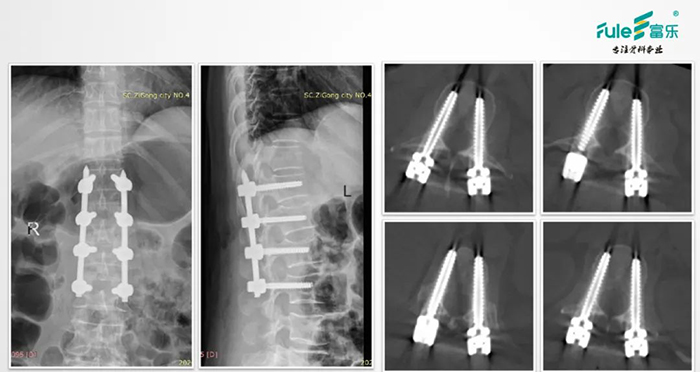

■术后——复查X片、CT,评估手术效果

![]()